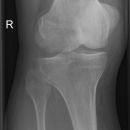

Kniegelenk a.p.

Frakturen im Bereich des Kniegelenks meist durch starke Gewalteinwirkung -> nach zusätzlichen Verletzungen fanden.

CAVE: CT-Indikation: bei V.a. Femurkondylenfraktur/Tibiakopffraktur

MRT-Indikation: zur Darstellung nichtossärer Gelenkanteile oder OD

Beurteilungskriterien

• Physiologisch leichte Valgusstellung von 7-9°. Mechanische Beinachse nach Miculicz (Traglinie Femurkopfzentrum – Mitte OSG) steht normalerweise senkrecht auf der Tangente an die Femurkondylen (Transversalebene des Kniegelenks)

• Weite des femorotibialen Gelenkspaltes beträgt 3-5 mm. Der Laterale erscheint aufgrund etwas kräftigerer Knorpelschicht etwas weiter.

• Weichteilkonturen, Kollateralbänder, Patella- und Quadrizepssehnenruptur: Unschärfe der jeweiligen Kontur.

• Target areas: Eminentia intercondylaris, Tibiaplateaukanten, Fibulaköpfchen